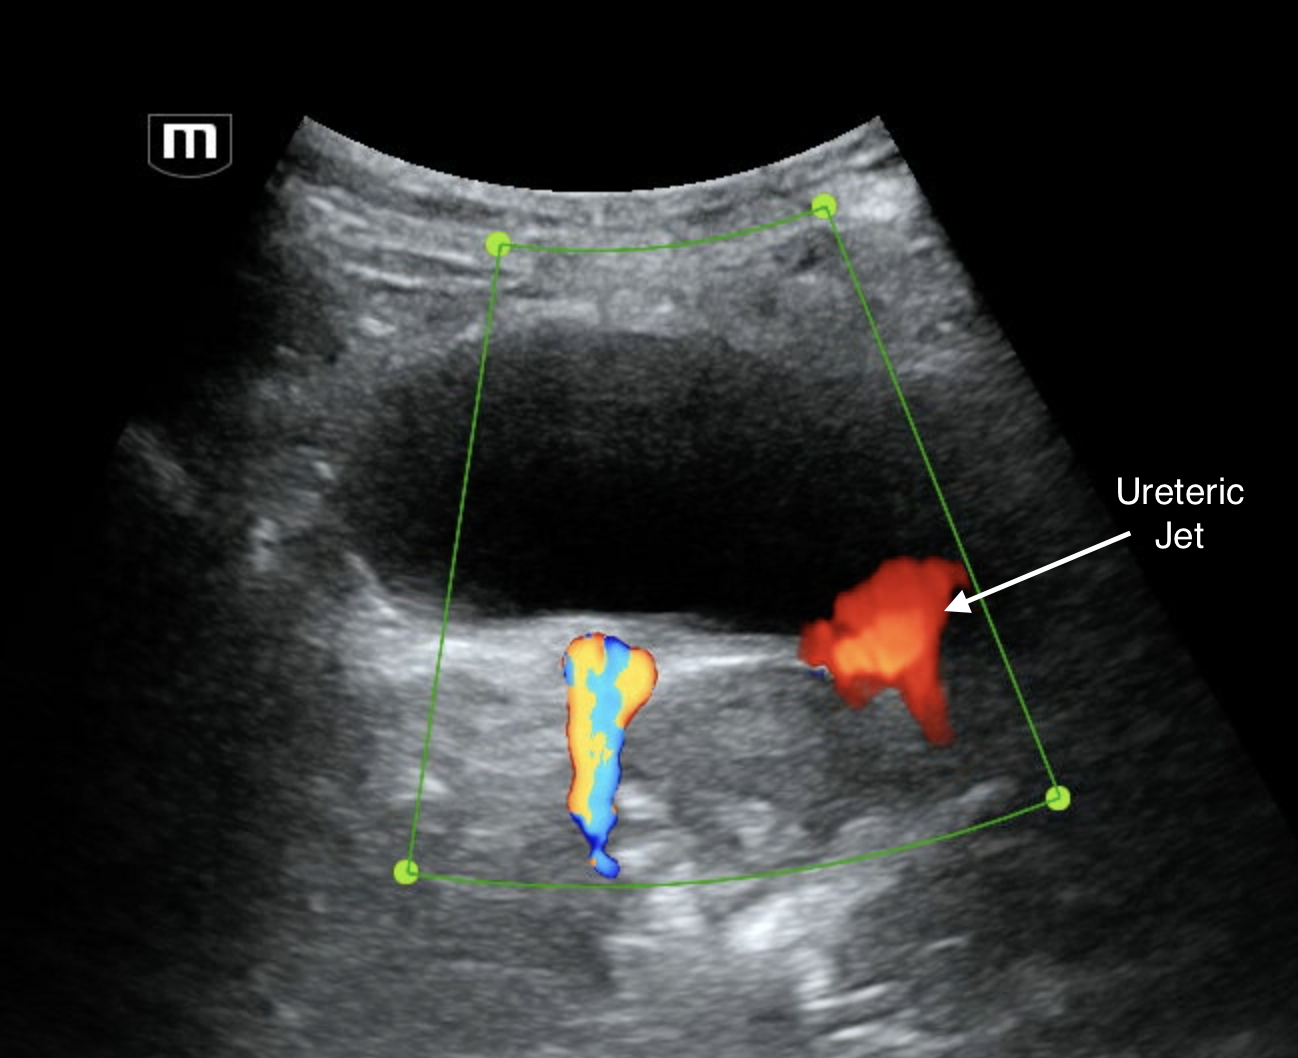

Examination of the bladder revealed a small hyperechoic linear structure at the VUJ (likely renal stone). Colour doppler on this revealed twinkle artefact which is typical for renal stones.

Intraureteric stones are typically seen best at the PUJ or the VUJ with ultrasound. The midureter is usually obscured by bowel gas. Ureteric stones are usually hyperechoic and colour doppler reveals a tail of vibrant colour reveberation artefact called the "twinkle" artefact. Often at the VUJ, the stones are small and blend in with the bladder muscle so decreasing gain to make the soft tissue hypoechoic and adding colour can increase your sensitivity. A full bladder also helps.

Pelvis trans: hyperechoic stone in R VUJ

Note that the measured size of a stone on US is usually unreliable.